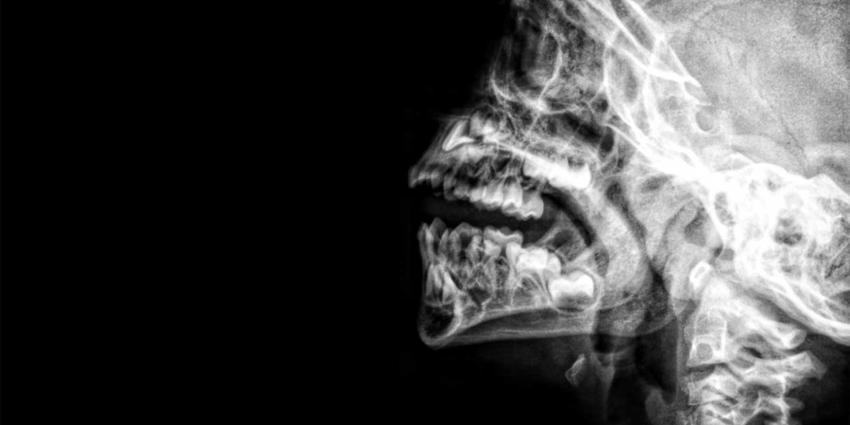

rontgen-schedel-nek-gebit

Foto: Unsplash/Umanoide